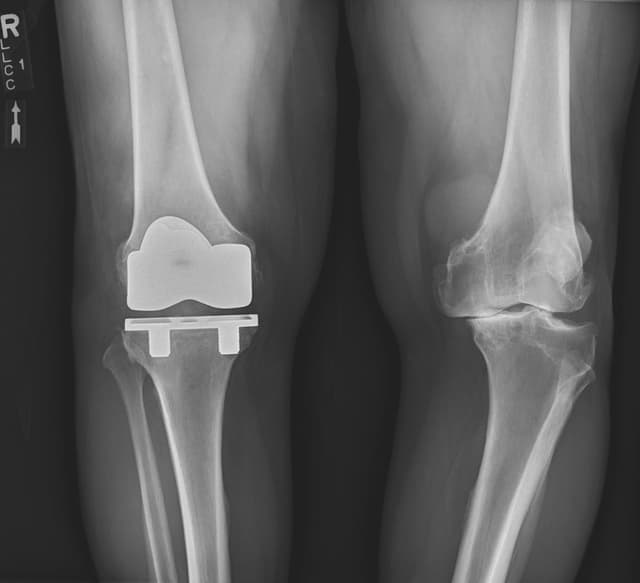

Total Knee Arthroplasty (Cementless, Robotic-assisted)

Imaging

Post-op